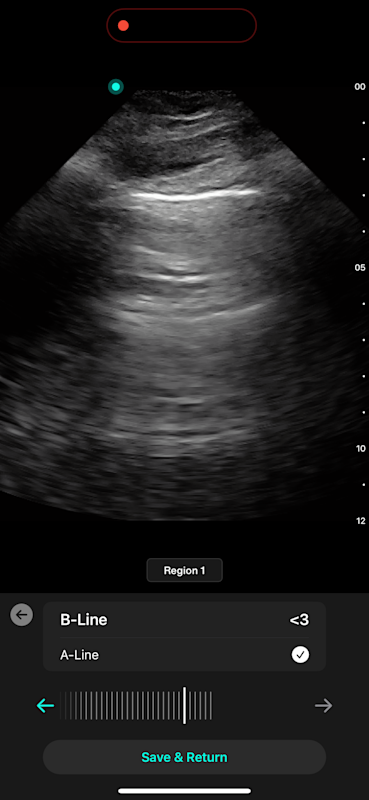

Lung AI

With Lung AI, you can determine the presence or absence of A-lines, B-lines, pleural effusion, and consolidation/atelectasis reliably in seconds.